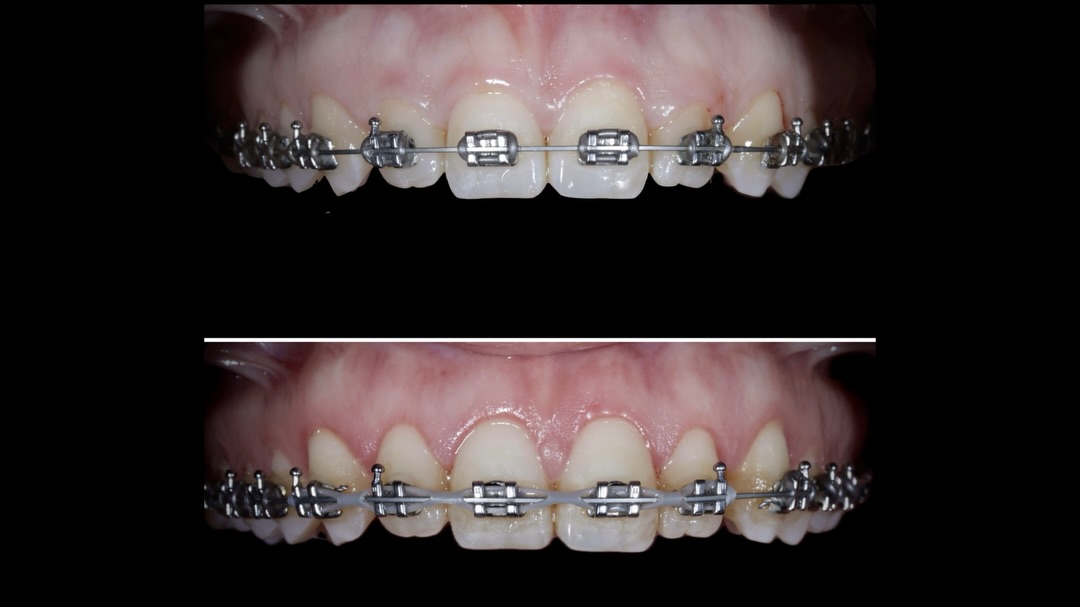

Formación Advance dirigida a doctores que quieran perfeccionar sus tratamientos de ortodoncia invisible y mejorar su planificación clínica.

Recomendada para doctores que ya trabajan con el sistema QuickSmile y para doctores que quieren profundizar en ortodoncia invisible, abordando